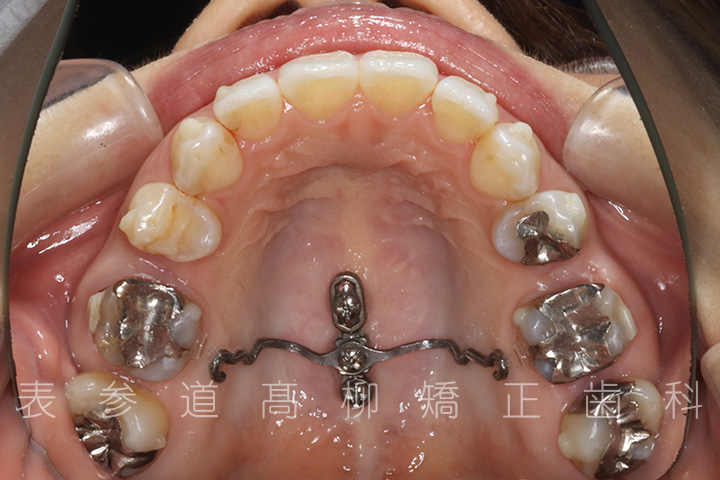

・上下両側第二小臼歯を抜歯

・マウスピース型矯正装置と歯科矯正用アンカースクリューを併用し、上顎臼歯部を圧下

・歯科矯正用アンカースクリュー(i-station)を併用し、前歯部を後方へ移動する

・歯科矯正用アンカースクリューを併用し、下顎大臼歯の近心移動(前方への移動)